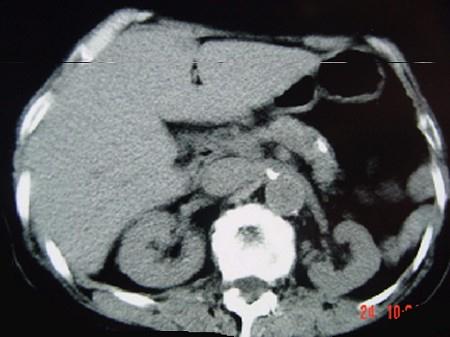

问题 女,54岁,中上腹痛,体重减轻,消化不良,脂肪痢、便量多、泡沫状。影像检查如下图,最佳诊断是 ( )

选项 A、急性出血坏死性胰腺炎 B、胰岛素瘤 C、慢性胰腺炎 D、胰腺癌 E、急性胰腺炎

答案 C